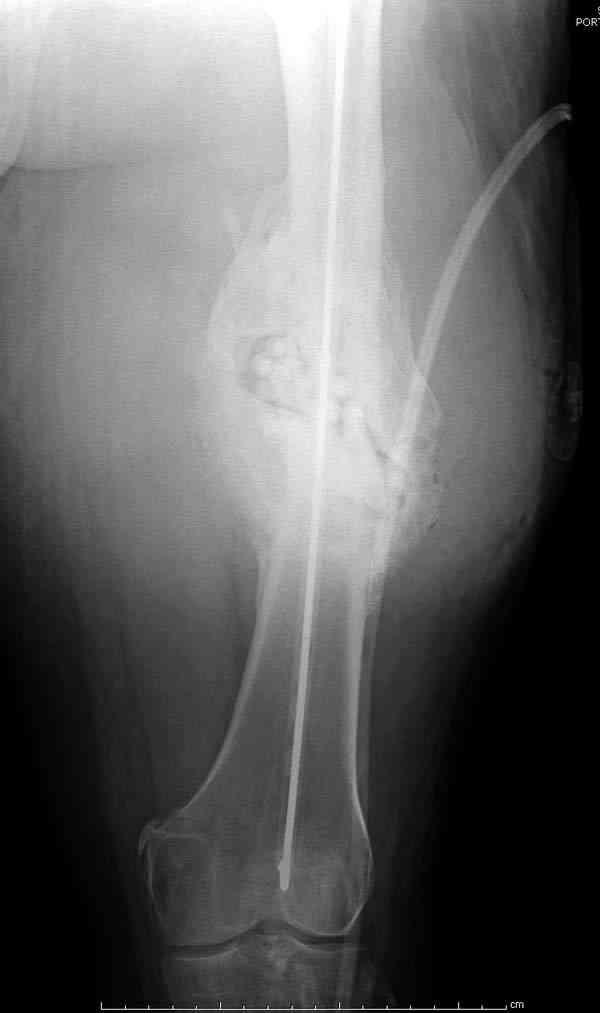

На ренгенограмме явный остеомиелит с секвестром, секвестерэктомия из медиального доступа и замена старого антибиотического гвоздя на новый.

После трех дней ваккуумного дренажа, из латерального доступа удаление остатков старых антибиотичеких бус, закрытие медиальной раны с наложением ваккуумирования латерально. В следующий раз, через пару дней надеемся закрыть рану.

удаление